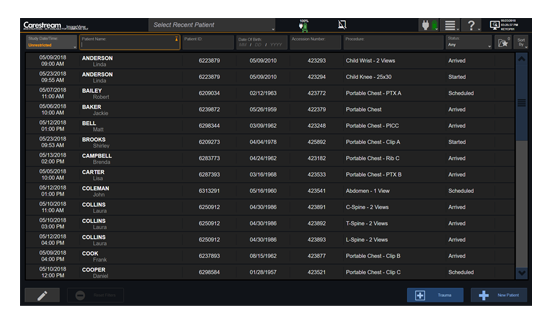

工作流智能。

在这里,先进的智能功能自动执行手动任务和工作流程步骤,以简化流程,提高技术人员工作效率,节省时间和金钱,并增强患者护理。

自动化设备定位和患者姿势确认可优化放射科技师的效率并加快工作流程。

自动技术选择可改善影像一致性并支持辐射剂量控制。

通过任务自动化功能改进感染控制,使放射科技师不再与潜在感染患者直接接触。